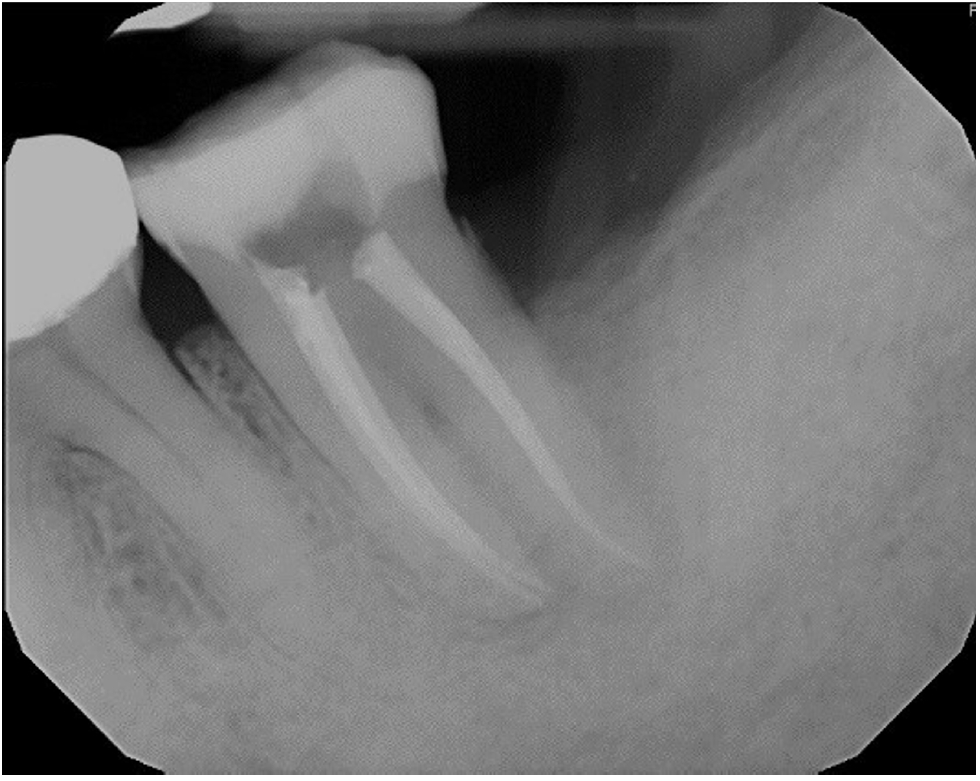

Working lengths were determined using an electronic apex locator (RootZX; J Morita, Kyoto, Japan) and confirmed with a periapical radiograph, which also showed a radiopaque fragment consistent with a cemental tear (Figure 2). The chamber was flooded with 5% sodium hypochlorite, and the canals were instrumented using size 8, 10, 15, and 20 K files, followed by a 25/.07 Primary Wave One Gold (Dentsply Sirona, Charlotte, NC, USA) reciprocating file. Irrigation was performed with 12 mL of 5% sodium hypochlorite with ultrasonic activation for 30 seconds per canal. Calcium hydroxide was placed as an intracanal medicament with a lentulo spiral, and the tooth was temporized with a sterile sponge and Cavit (3M ESPE, St. Paul, MN, USA). The patient was informed to return in 2 weeks for completion of the root canal.

Figure 2.

Working length radiograph showing radiopaque fragment consistent with a cemental tear along distal root (red arrow).

rde-2025-50-e31f2.jpg

Figure 2. Working length radiograph showing radiopaque fragment consistent with a cemental tear along distal root (red arrow).